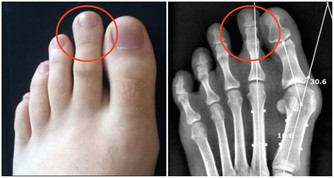

膝關節尤其是人體所有關節、軟骨構造中最為複雜的部位,

包括髕骨、大腿股骨、小腿脛骨、兩個半月狀軟骨及四條韌帶,活動機轉相當複雜。

加上膝關節必須承受人體全部或數倍的重量,

加上日常跑、跳、上下樓梯、背負重物、穿高跟鞋等因素,

膝蓋的受力更大,是全身關節中最容易退化的部位。

膝關節

膝關節可以說是退化性關節炎的最大宗。關節就如同車子的輪胎般,如果常煞車、摩擦多,輪胎就會提早報銷。門診中患者常見的主述症狀如下:

⑴疼痛加上軟痠及卡住的感覺,多屬半月軟骨的問題。

⑵下樓梯時膝蓋痠軟,多屬髕骨軟化,以女性居多。

⑶從坐姿站起時兩腿感到痠軟,通常屬於骨小樑退化。

⑷關節感到卡卡的,且無法伸直或彎曲,則是半月板破裂。

治療:一般來說,膝部退化性關節炎兩腳都會發生,但病變的程度不一定是相同的。膝部退化性關節炎除了復健治療外,也會以藥物來緩解疼痛。此外,於關節內注射玻尿酸,也被證實能改善症狀。

當上述保守療法無法解決疼痛,才考慮施以手術治療,年輕患者主要是透過關節鏡手術清除清除異物及病灶,年紀大者會施予人工關節置換術。